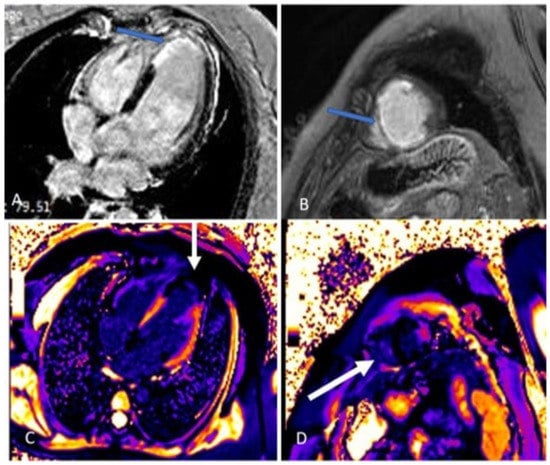

(A–D). The kinetic estimation by cardiac magnetic resonance (CMR) showed that apical segments of LV were akinetic to dyskinetic, and LVEF was 44% (Video S6). In figure parts (A,B), four chamber and short axis views are presented. Late gadolinium enhancement (LGE) was seen in the sub-endocardium in the medio-apical part of the septum and transmural LGE was seen in the apical parts of the septum and inferior, posterior, and anterior walls of LV (blue arrow). In figure parts (C,D), the zone of fibrosis, which was the zone of infarction, was present in apical segments of LV when using post-contrast T1 mapping (white arrow). Besides that, a high T1 signal was present in the peri-infarct area. Qualitative differences in infarct size which are calculated as (LGE mass/total LV mass) × 100 by CMR were discovered in the pattern of myocardial injury. In our patient, the size of fibrosis (infarct size) was 13%.